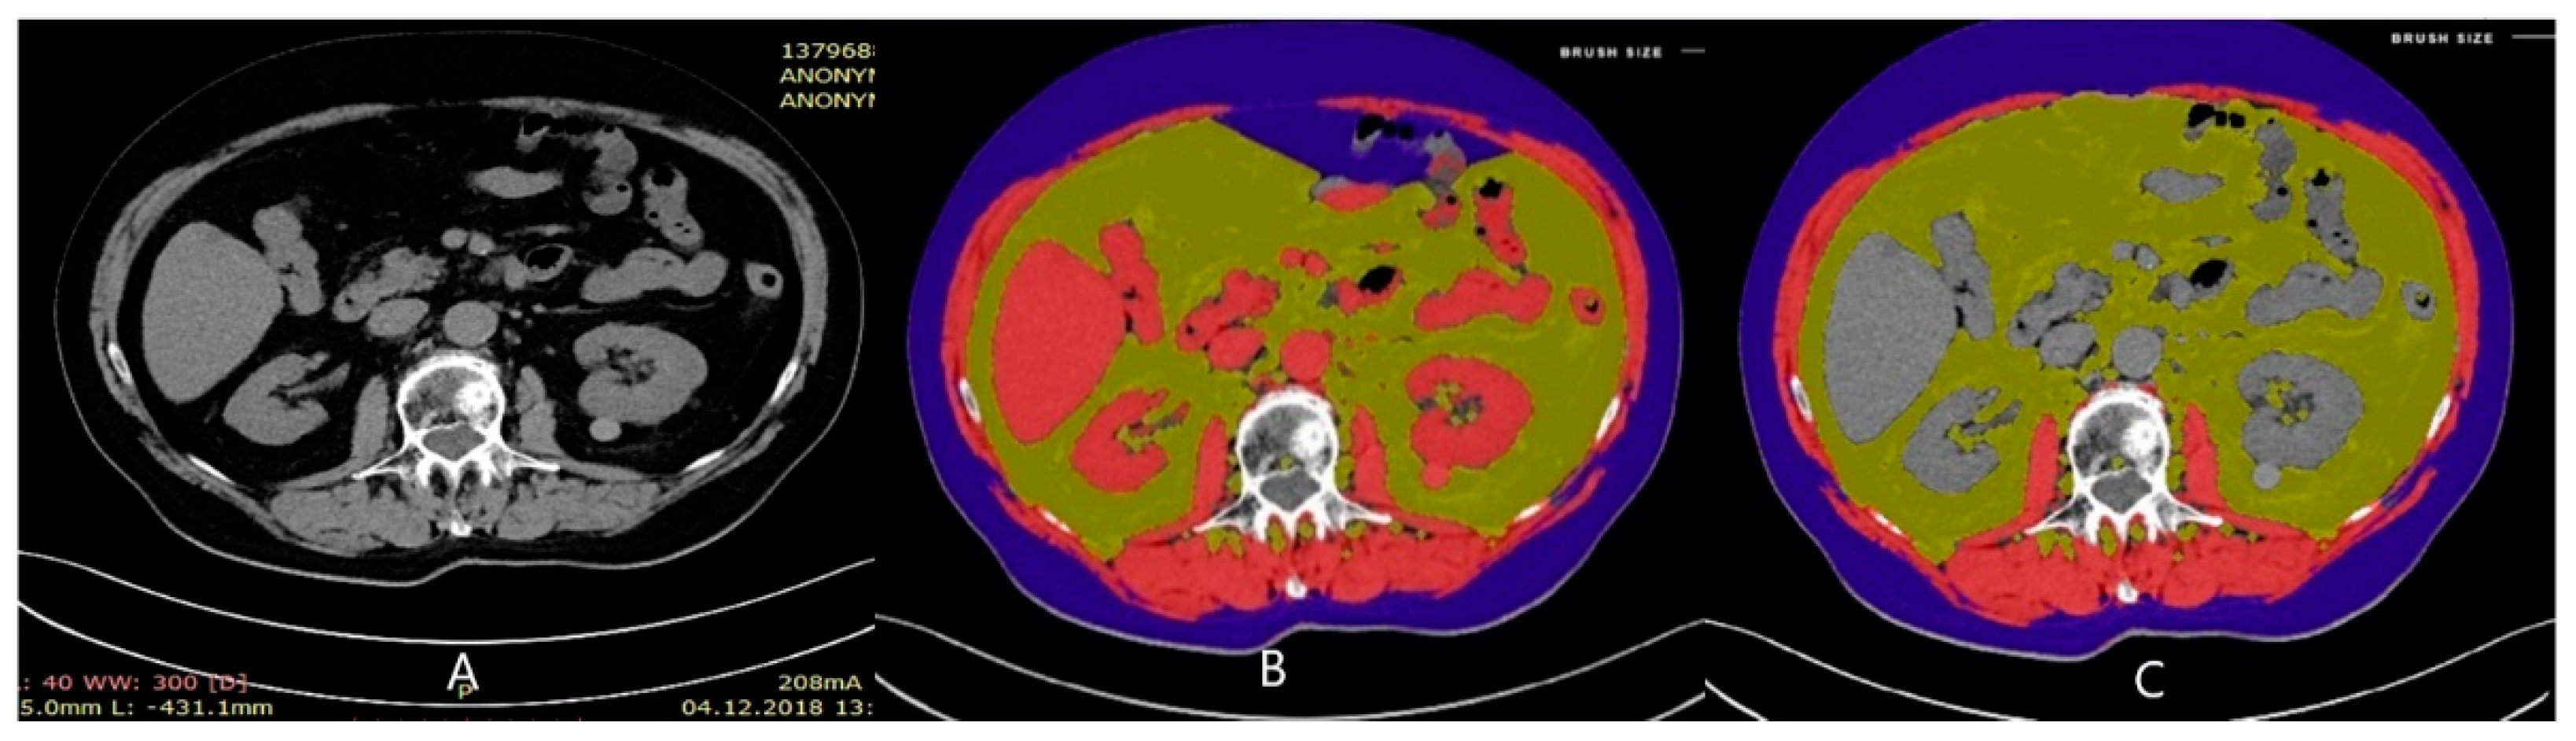

- Available online: https://coreslicer.com/ (accessed on 20 January 2022).